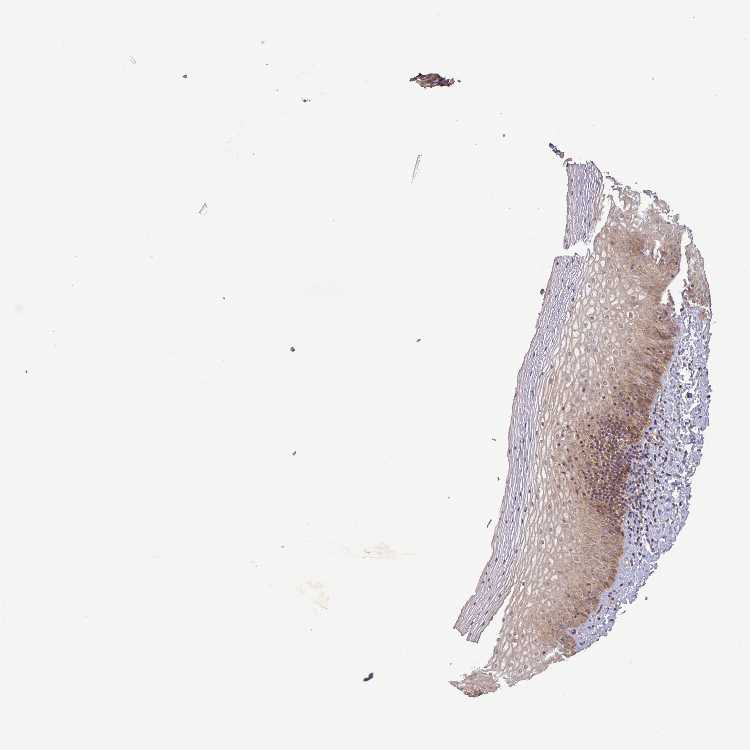

VAGINA - Antibody stainingi

Antibody staining in the annotated cell types in the current human tissue is reported as not detected, low, medium, or high, based on conventional immunohistochemistry profiling in selected tissues. This score is based on the combination of the staining intensity and fraction of stained cells.

Each image is clickable and will lead to virtual microscopy that enables deeper exploration of all samples and also displays staining intensity scores, fraction scores and subcellular localization as well as patient and tissue information for each sample.

Antibody HPA051636

Squamous epithelial cells Medium